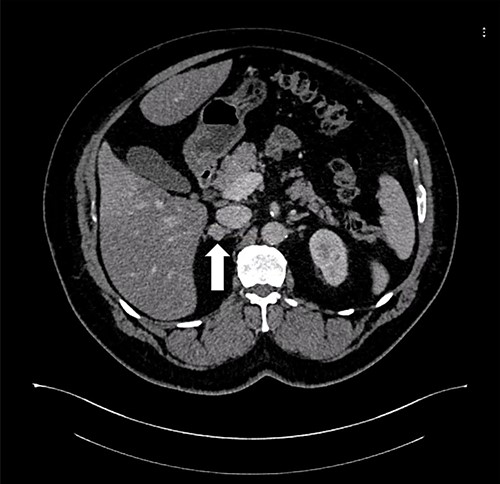

Patient 1 is a 45-year-old male, who came to our private clinic complaining of obesity with a body mass index (BMI) of 41 kg/m2. His other comorbidities included hypertension (HTN) controlled on one anti-HTN medication and diabetes mellitus (DM) on oral hypoglycemic agents (OHA). He denied any symptoms of reflux or any family history of adrenal/thyroid/parathyroid diseases. He was discovered to have a 4 cm right adrenal incidentaloma on a contrast-enhanced computed tomography (CECT) of the abdomen as a workup for abdominal pain (Fig. 1). Preoperative preparation included obesity workup with complete blood count, coagulation profile and a chest X-ray. Endocrine workup included a screening for possible functional incidentaloma, with adrenocorticotropic hormone of 2.8 pmol/l, aldosterone/renin ratio (ARR) of 1.7 ng/dl per ng/(ml·h), serum metanephrine of 343 pg/ml (reference <90), serum normetanephrine of 401 pg/ml (reference <129) and a normal serum morning cortisol of 168 nmol/l (reference 101–535). A diagnosis of right adrenal pheochromocytoma was established. A cardiac consultation was done and determined that the patient is fit for surgery and formulated a preoperative medication with α- and β-blockers.

Axial CT of the abdomen showing the right adrenal mass in Patient 1 (white arrow).